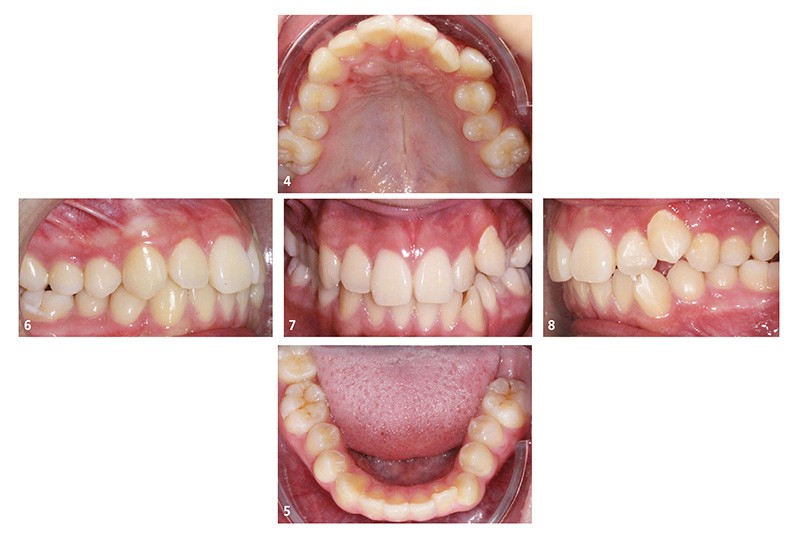

Sur le plan dentaire, au maxillaire, le patient présente une arcade en lyre avec de nombreuses malpositions (fig. 4). À la mandibule, la 37 est absente de l’arcade (fig. 5). Le patient présente une classe I d’Angle droite et gauche (fig. 6 et 7). Le surplomb et le recouvrement sont satisfaisants, les milieux sont alignés, et il existe une occlusion inversée 22/33 (fig. 8).